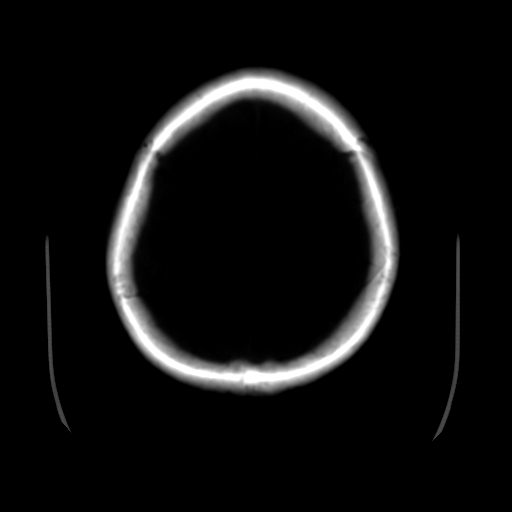

男,51岁,头外伤一小时,呕吐两次。

1)左侧中颅窝蝶骨翼后方硬膜外血肿。2)左侧颞顶部硬膜下血肿。3)蛛网膜下腔出血。4)左侧筛窦及双侧蝶窦炎症(或积血)。5)左侧额部头皮软组织肿胀。